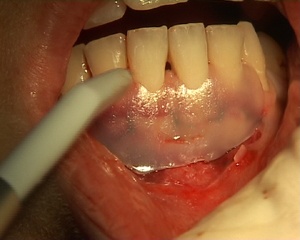

L'indication de greffe épithèlio-conjonctive a été posée pour traiter une récession gingivale. L'auteur utilise pour le prélèvement du greffon l'épitome de Klewansky et pour la protection du site donneur de l'histoacryl. La protection du site receveur est assurée par un pansement temporaire photopolymérisable